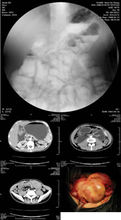

1.3 X線鋇餐檢查:可見小腸受壓、緊縮、小腸整塊移動或迴腸末段狹窄等徵象,鋇劑通過小腸的時間明顯延長,短縮的腸系膜及纖維內壁的粘連可使小腸出現類似結腸袋樣的徵象。

1.4 CT檢查:可了解腹塊內為摺疊之小腸,腸管狹窄為增厚的腹膜所包裹。

2.3 X線可發現全部或部分小腸聚攏於某一部分,位置固定。

2.4 B超可見內有腸管的腫塊。